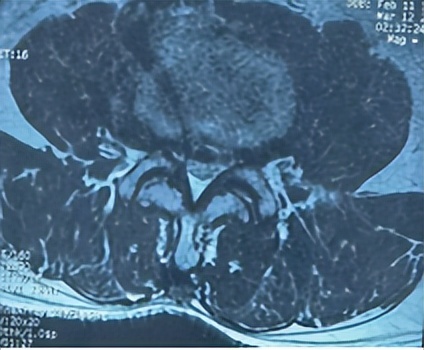

腰3/4、腰4/5两个节段椎管狭窄

66岁男性患者,腰3/4、腰4/5两个节段椎管狭窄,左下肢放射性疼痛、麻木2个月余,间歇性跛行,保守治疗无效。其爱人9年前患腰椎间盘突出症,副主任医师石立刚利用微创椎间孔镜治疗后,至今效果满意。此次慕名前来。